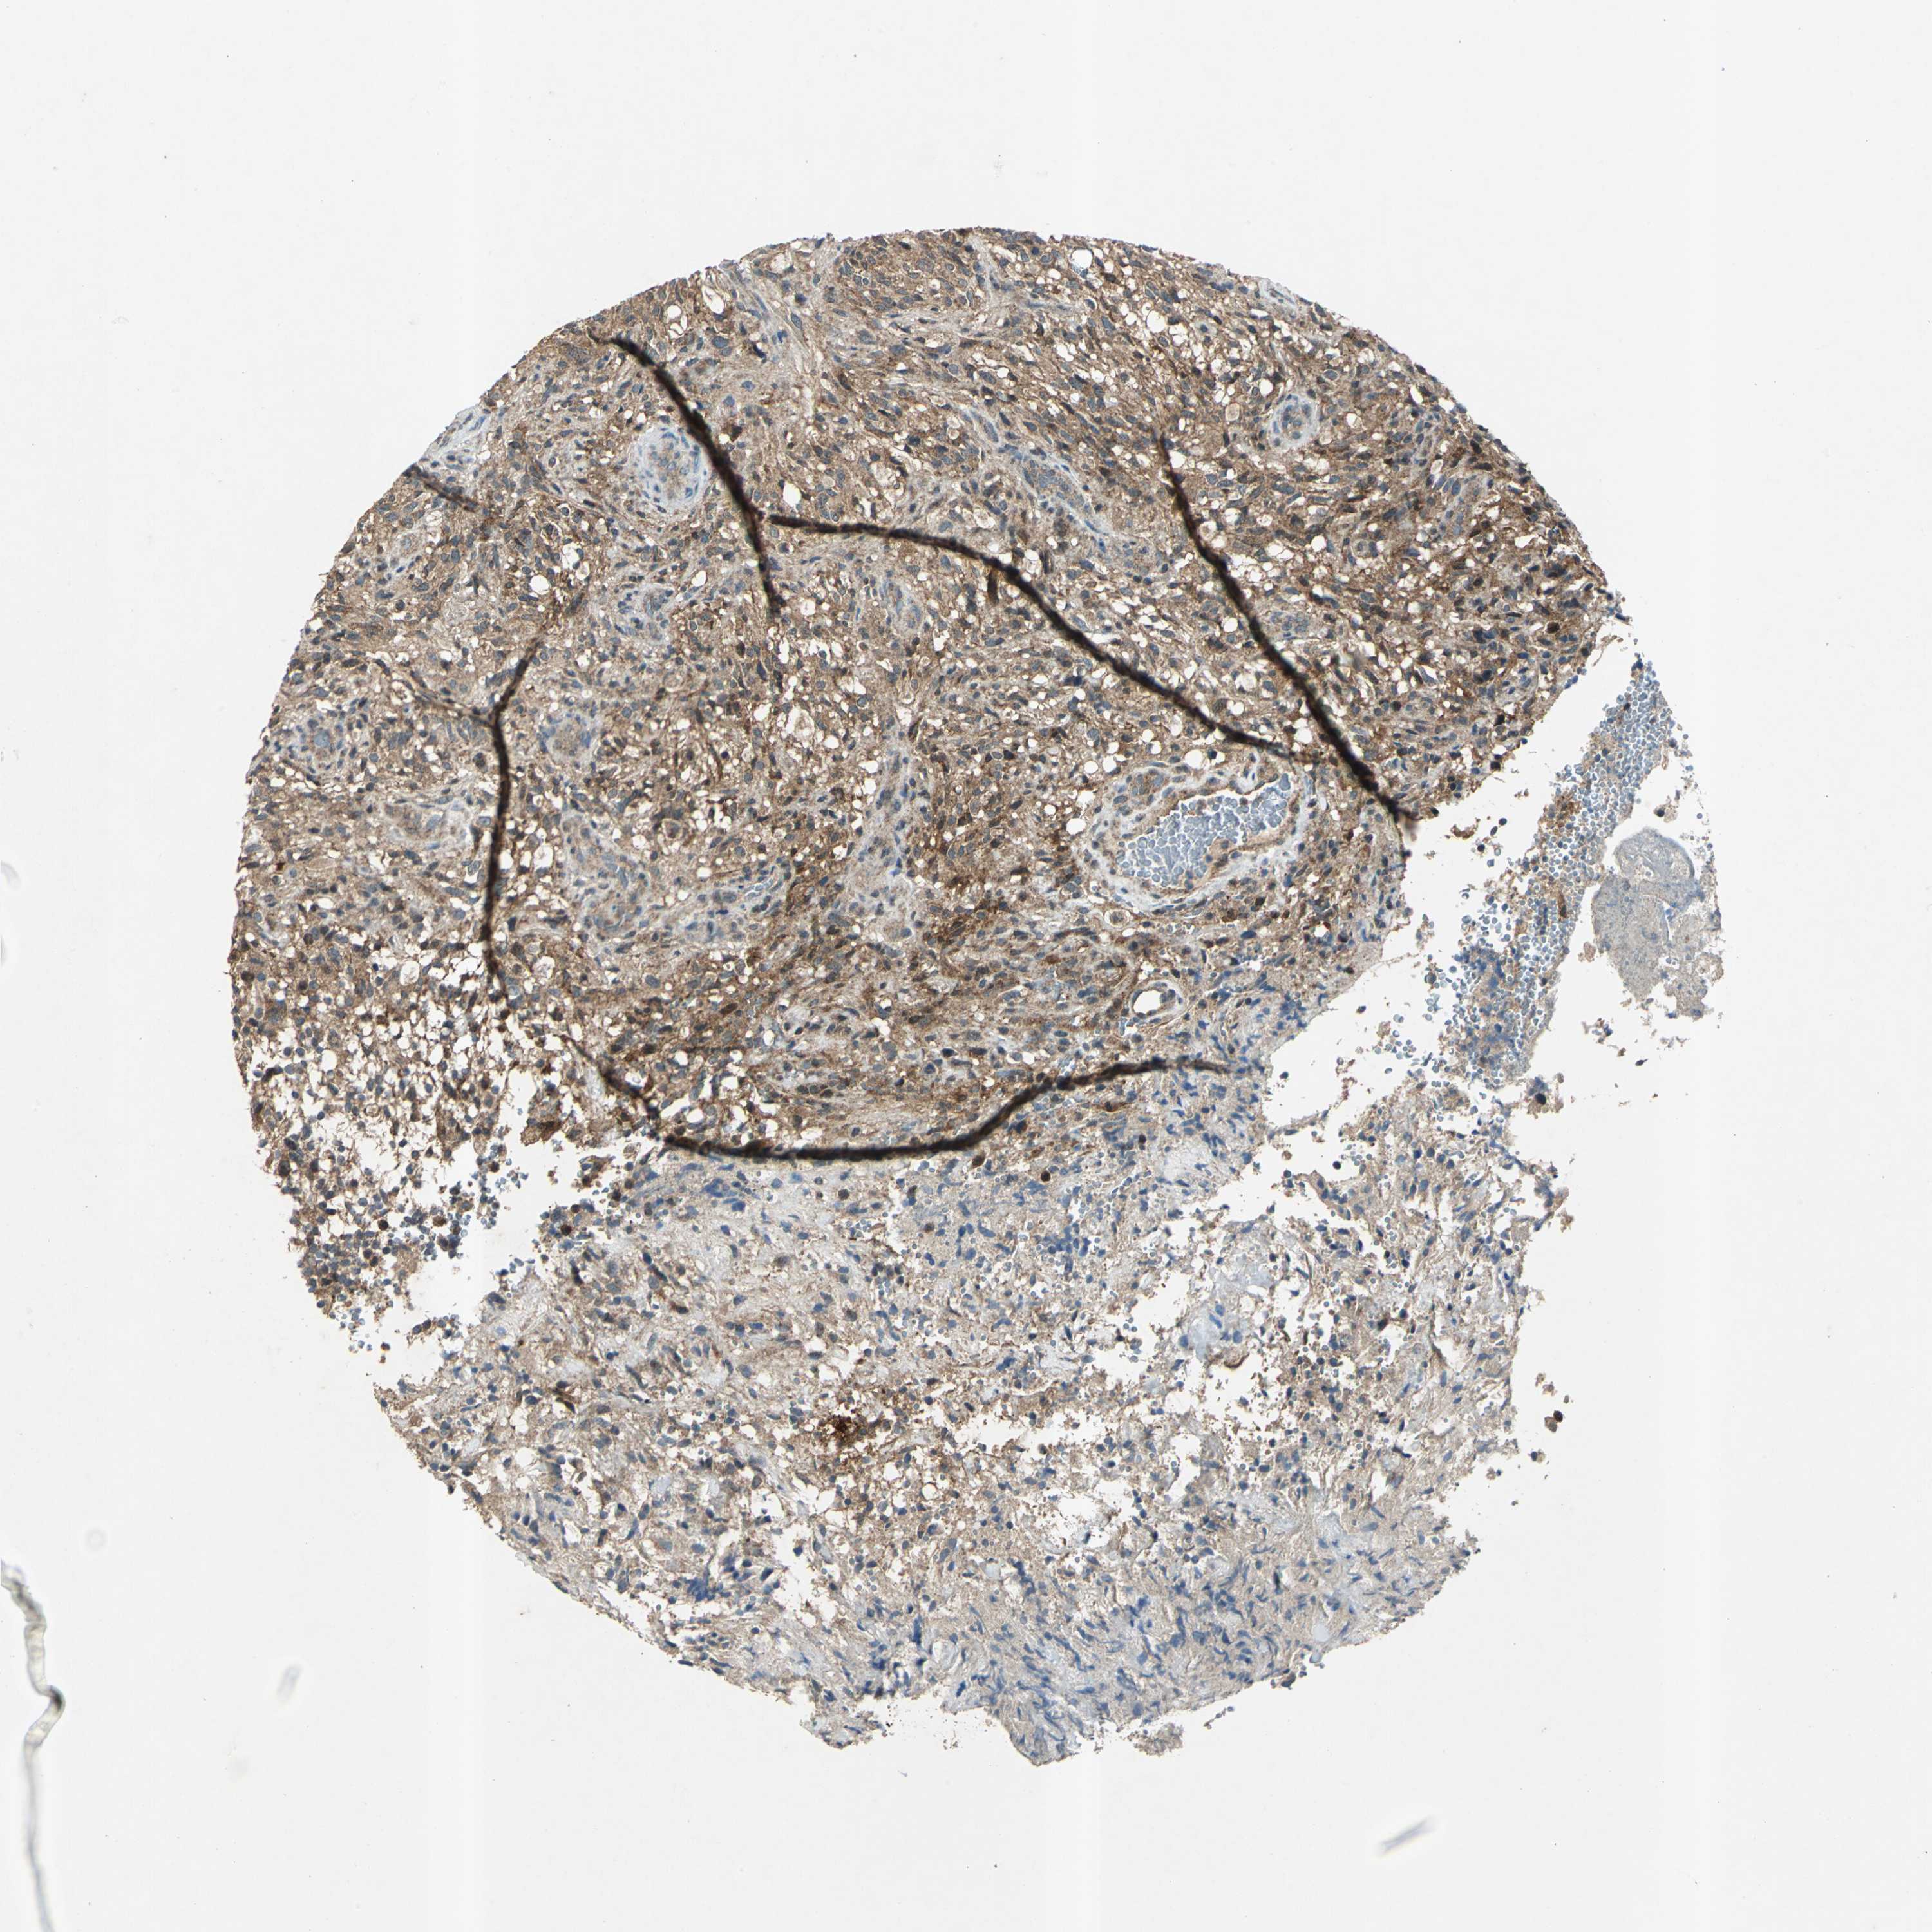

GLIOMA - Protein expressioni

A mouse-over function shows sample information and annotation data. Click on an image to view it in a full screen mode. Samples can be filtered based on level of antibody staining by selecting one or several of the following categories: high, medium, low and not detected. The assay and annotation is described here.

Note that samples used for immunohistochemistry by the Human Protein Atlas do not correspond to samples in the TCGA dataset.

Antibody stainingi

Antibody staining in the annotated cell types in the current human tissue is reported as not detected, low, medium, or high, based on conventional immunohistochemistry profiling in selected tissues. This score is based on the combination of the staining intensity and fraction of stained cells.

Each image is clickable and will lead to virtual microscopy that enables deeper exploration of all samples and also displays staining intensity scores, fraction scores and subcellular localization as well as patient and tissue information for each sample.

Antibody HPA000903

Antibody CAB006244

Staining

High

Medium

Low

Not detected

Intensity

Strong

Moderate

Weak

Negative

Quantity

>75%

75%-25%

<25%

None

Location

Nuclear

Cytoplasmic/membranous

Cytoplasmic/membranous,nuclear

Glioma, malignant, High grade

Glioma, malignant, Low grade

Glioma, malignant, NOS